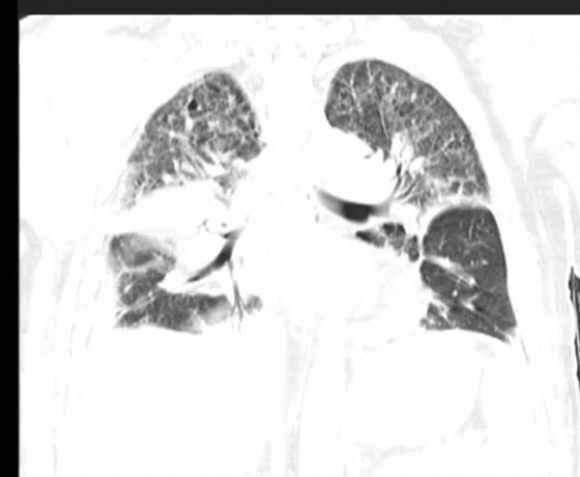

Ngày 16/5, anh Lưu được đưa đến Khoa Cấp cứu tại Bệnh viện Nhân dân tỉnh Hồ Nam (Trung Quốc) trong tình trạng sốt trên 40 độ C. Kết quả kiểm tra CT phát hiện tràn dịch 2 bên ngực, viêm phổi cấp, xét nghiệm máu cho thấy xuất hiện tình trạng giảm oxy máu nghiêm trọng, suy hô hấp, buộc phải thở máy, lập tức chuyển đến phòng cấp cứu đặc biệt (EICU).

Tổn thương phổi do Legionella pneumophila gây ra.